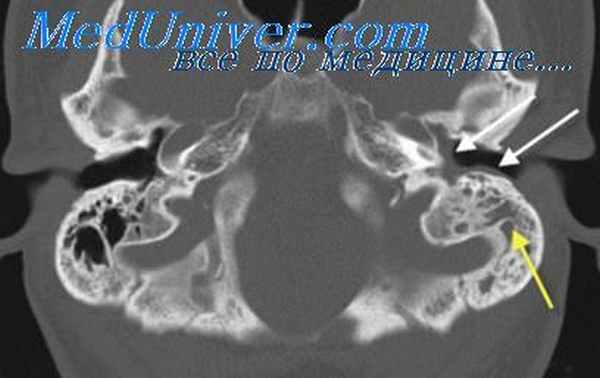

Поставить точный диагноз удается уже при визуальном осмотре заушной области головы пациента. Затруднения в диагностике может вызвать только атипичный мастоидит, когда симптомы либо полностью отсутствуют, либо выражены достаточно слабо, либо схожи с проявлениями целого ряда инфекционных заболеваний. В числе дополнительных исследований инструментальной и лабораторной диагностики – отоскопия, микроотоскопия, бактериологический посев выделений из уха, рентгенография и компьютерная томография. На снимке височной области четко визуализируются завуалированные ячейки, «закупоренные» гнойным содержимым, и едва различимые перегородки. При необходимости к диагностике привлекаются нейрохирург, стоматолог, офтальмолог и прочие узкоспециализированные врачи.

Первые признаки костных изменений в сосцевидном отростке, т. е. осложнения острого среднего отита мастоидитом, наступают не в строго определенный срок. По мнению Я. Г. Диллона, мастоидит рентгенологически может быть установлен в конце первой или в начале второй недели заболевания. Л. Т. Левин и Я. С. Темкин считают, что при выраженных явлениях костной рарефикации в перегородках клеток длительность процесса соответствует приблизительно четырехнедельному сроку после начала заболевания, а при менее резко выраженных явлениях остеоклаза—периоду от 10 дней до 4 недель.

Локализация первичных изменений у взрослых соответствует очень часто терминальным и перисинуозным клеткам сосцевидного отростка. С. И. Вульфсон, Я. Б. Каплан, Д. Г. Рохлин и С. А. Рейнберг отмечают частое поражение группы клеток между сигмовидным синусом и лицевым нервом. У детей при отсутствии клеток в самом сосцевидном отростке изменения наблюдаются в клетках периантральной области.

Начальным рентгенологическим признаком пролиферативно-эксудативной стадии мастоидита следует считать уменьшение интенсивности тончайших теневых линий, образованных стенками наслаивающихся друг на друга многочисленных клеток отростка. Этот признак объясняется рарефикацией костной ткани перегородок клеток, их остеопорозом. Рентгенологически возможно и очень существенно своевременно обнаружить симптом полного гнойного расплавления кости, характерный для последующего развития мастоидита с образованием костного абсцесса.

Трудности раннего определения симптома деструкции перегородок клеток, которая чаще возникает в каком-либо ограниченном участке сосцевидного отростка, заключаются в невозможности на первых порах различить деструктивный очаг, находящийся в толще большого количества клеток, прикрывающих его своей ячеистой структурой. С увеличением размеров очага его удается обнаружить на рентгенограмме по двум признакам: полное исчезновение структуры перегородок клеток и возникновение просветления в его области.

Этот феномен мы называем симптомом вторичного просветления, который, так же как и при мукоцеле придаточных пазух носа, обусловлен уменьшением поглощения рентгеновых лучей на месте участка костной деструкции. Полное разрушение костной ткани сосцевидного отростка при субпериостальном абсцессе приводит к образованию интенсивного гомогенного очага просветления, лишенного какой-либо структуры.

Если этот очаг образуется из большого числа мелких клеток, границы его не имеют правильных очертаний и характера тонких линейных теней. Когда же очаг образуется из двух-трех крупных клеток сосцевидного отростка после разрушения разделяющих их перегородок, контуры очага могут быть правильными и представлять собой тонкие теневые линии, если стенки общей полости сохраняют свою целость.

Мы наблюдали вариант сосцевидного отростка с крупной солитарной клеткой, которая при наличии острого отита могла быть принята за очаг деструкции из-за относительной прозрачности ее огромной полости. Во избежание ошибочного диагноза мастоидита и костного абсцесса н подобных случаях следует помнить об анатомическом варианте крупной солитарной клетки, имеющей на рентгенограмме свои отличительные признаки: правильные очертания и линейную теневую границу ее стенки.

Локализация костного абсцесса при мастоидите и особенности анатомического строения височной кости определяют клинические симптомы и рентгенологическую семиотику. Так, имеются основания предполагать перисинуозный абсцесс в том случае, когда очаг деструкции располагается в области синуса, или бецольдовскую форму мастоидита, когда он находится на самой верхушке отростка.

При латентно протекающих, скрытых формах мастоидита рентгенологически нередко обнаруживается спонгиозно-пневматический тип строения височной кости с небольшим количеством периантральных и перисинуозных клеток и отсутствием их на верхушке отростка, имеющего толстый наружный кортикальный слой. Значение рентгенологического распознавания латентного мастоидита очень велико, так как при отсутствии характерных клинических симптомов в глубине сосцевидного отростка под толстым корковым слоем может быть своевременно обнаружен очаг костной деструкции.